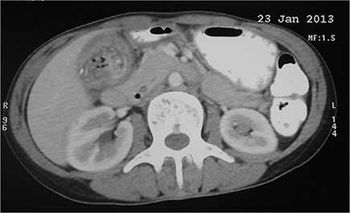

Case History: A 44-year-old female admitted with severe, colicky right upper quadrant pain radiating through to her back and one episode of vomiting of gallstones.